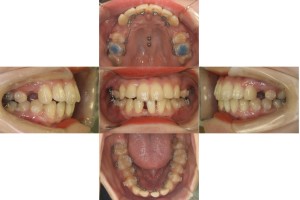

現在の歯並びだと、下の歯が上の歯の装置にぶつかってしまうため、上の奥歯に「バイトアップ」という青い材料をつけてかみ合わせをあげています。